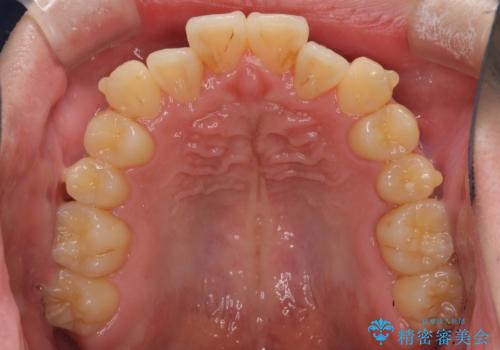

前歯のクロスバイト インビザラインによる矯正治療

- 上下のクロスバイトと前歯のデコボコを気にして来院された患者様です。

インビザラインを用い、IPR(歯と歯の間を削る)と歯列全体を拡大させることで、歯並びを整えていくこととしました。

上下ともに歯列全体を後方に移動させるため、上下の親知らずを抜歯することとしました。